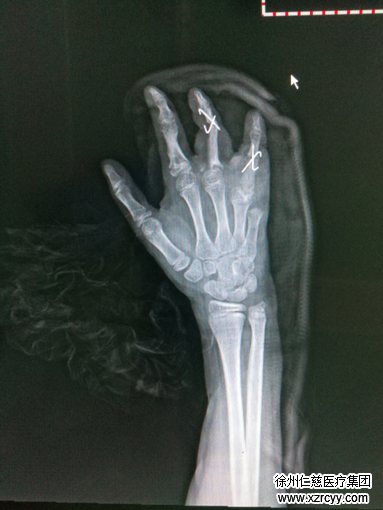

“啊~我的手~妈快来……”听到喊叫的母亲急忙赶来,第一时间关掉机器。中间过程虽仅有1分多钟,可小梓的右手已被玉米机严重“咬伤”,右手中、环、小指多发骨折缺损伴掌指关节脱位,右手第4、5掌骨头端骨折,血肉模糊。

“与成年人相比,小孩的血管更细,且骨骼未发育成熟,手术难度较成人大很多。”小梓才10岁,如果受伤手指离断的话,对以后生活影响非常大。综合考虑多方因素,黎医生为小梓量身制定了“先期清创骨折复位肌腱血管修复 +后期髂骨植骨置于右环指近节指骨缺损处”的两步走手术方案。